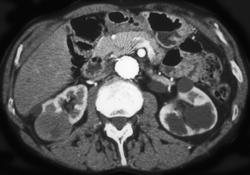

Renal Cell Invades Inferior Vena Cava (IVC)